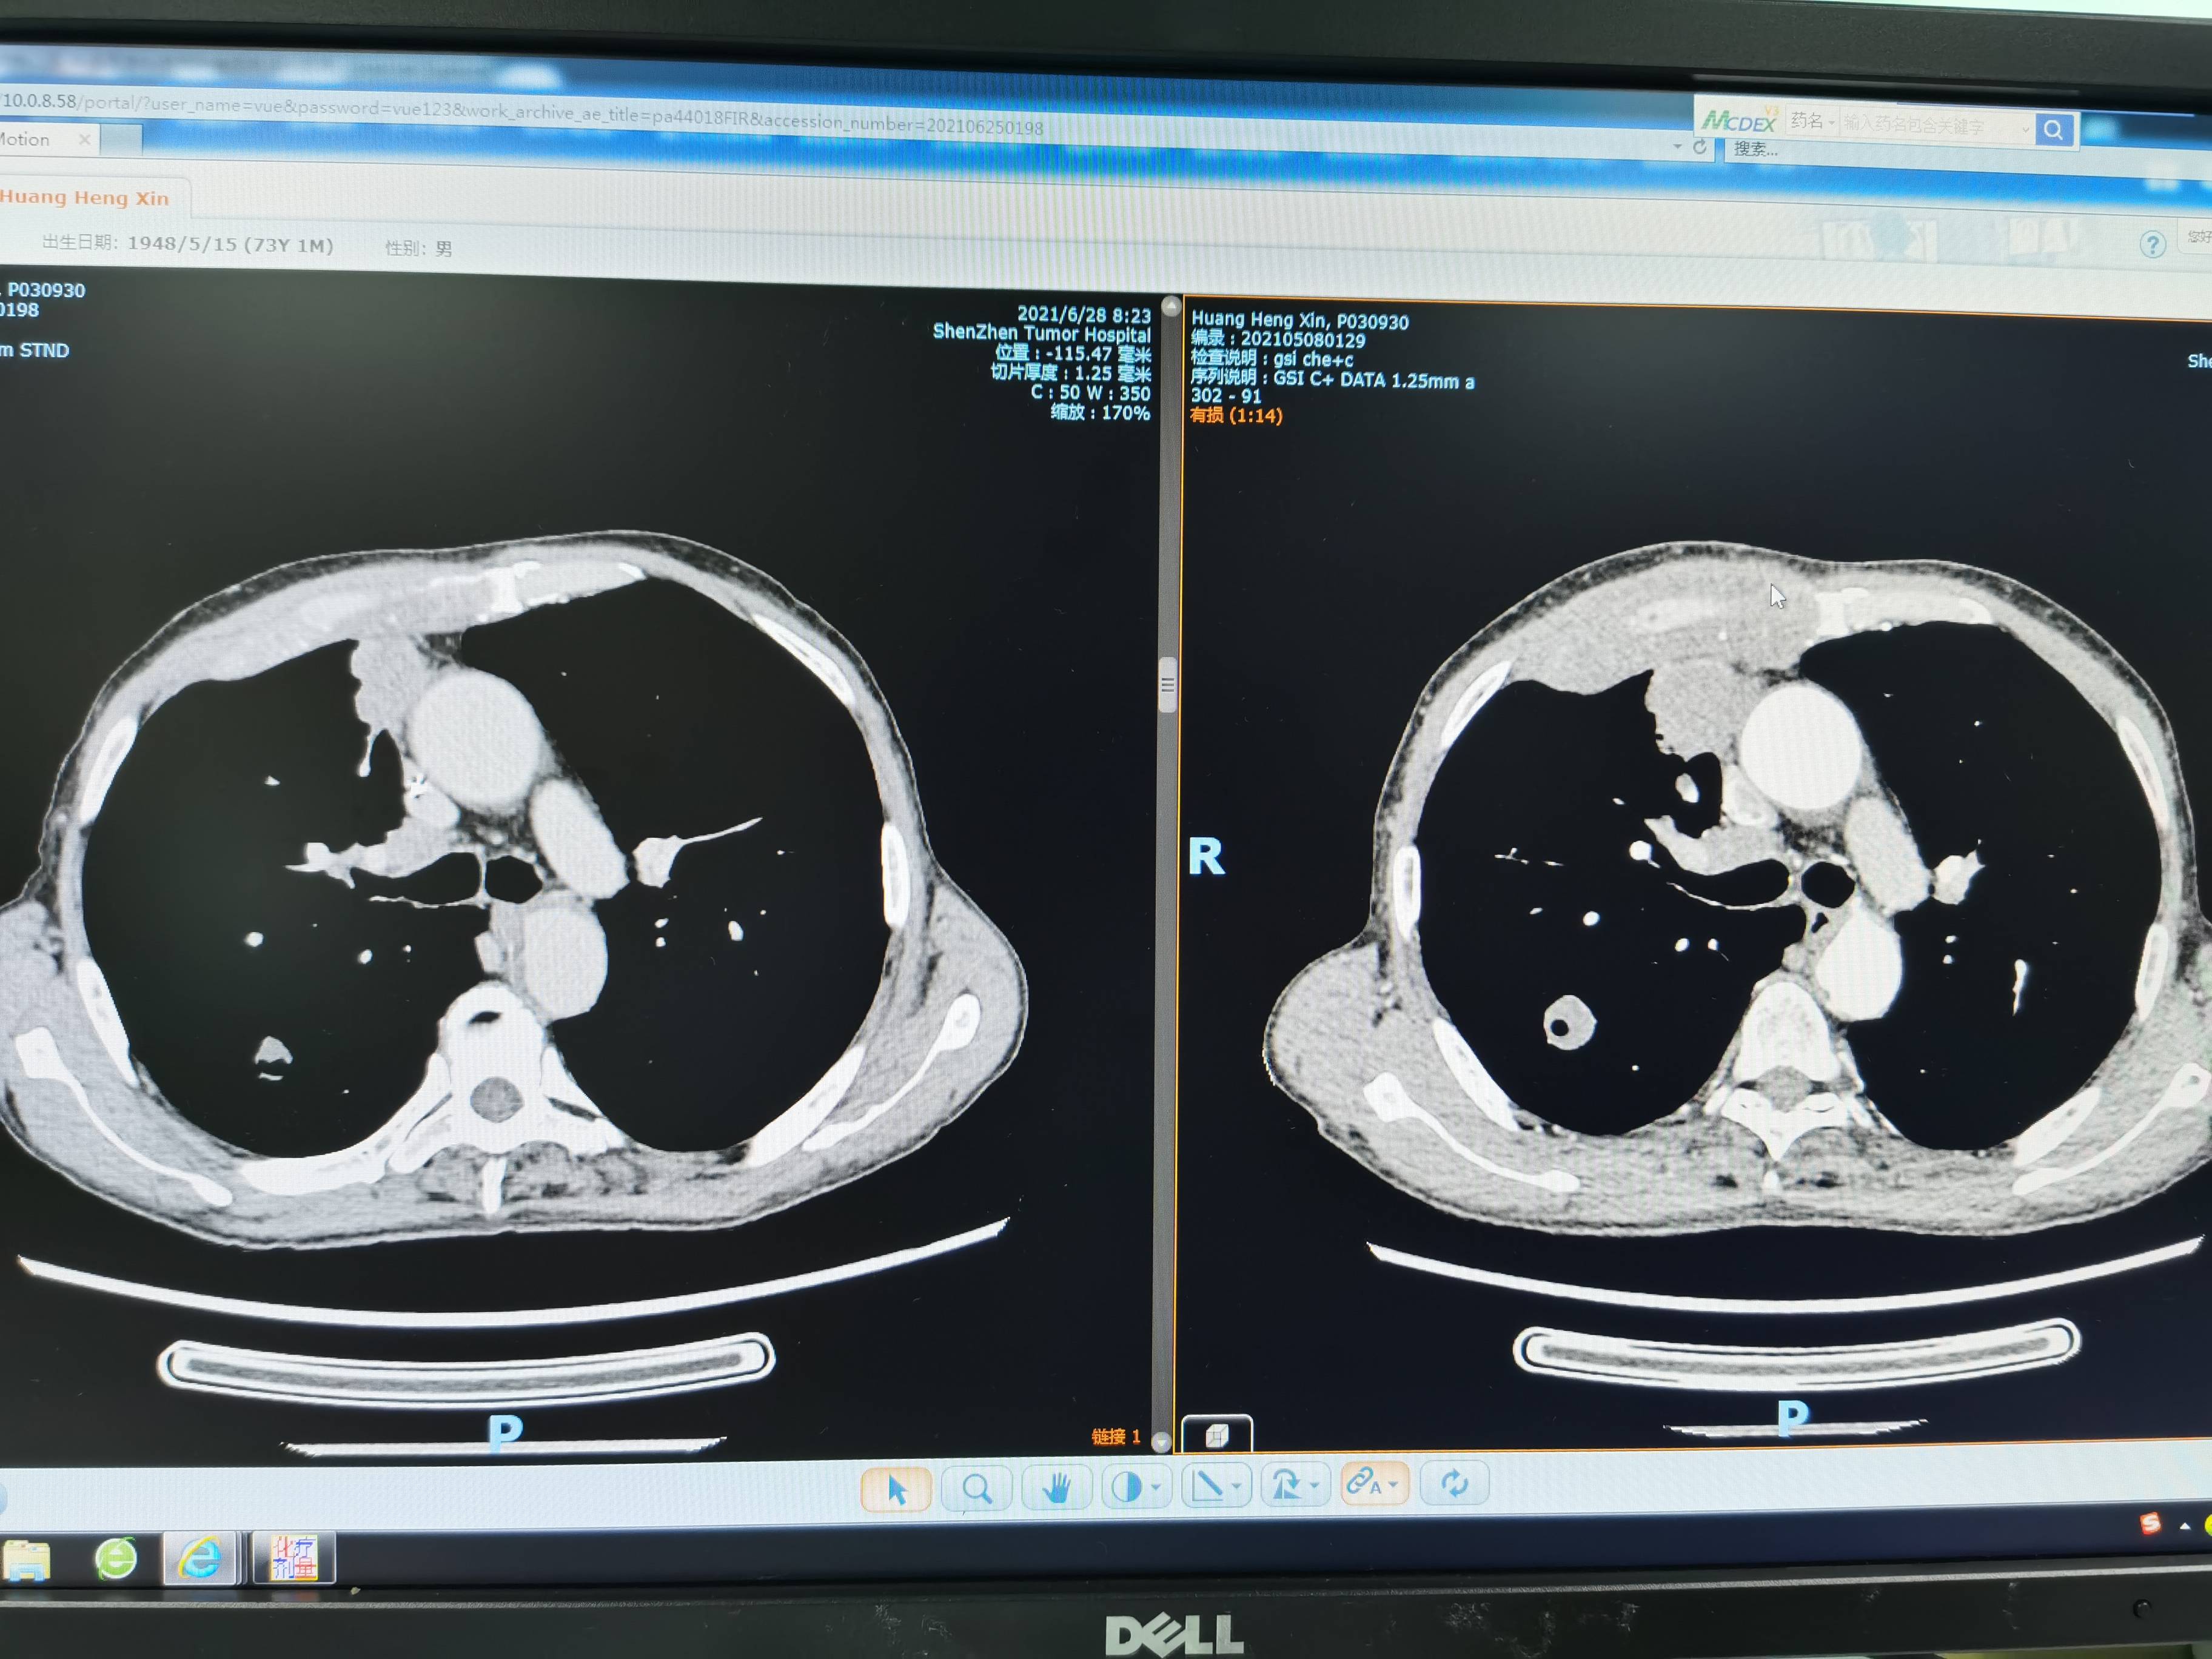

一般来说,二化周期后三化的时间点会有CT的复查,我们也不例外,也提醒主治医师别忘记安排。CT的结果还是不错的,有缩小,这也说明肿瘤发展暂时控制住了,其实不做CT我也能预想到这个结果,因为我爸的体感变好,肋骨疼痛也减轻或者没有,偶有白痰易咳出。不发烧,副作用方面就回家复查血常规,打两针低剂量升白针。三餐正常,所以本次CT算是预期内,而且本来前两化的效果大多数都比较理想的。

左边是治疗后,右边是治疗前